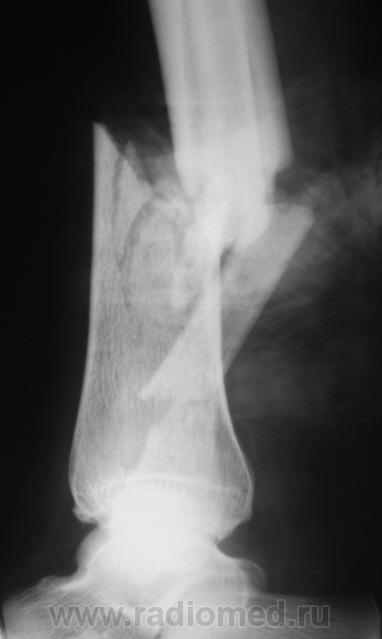

Наверное, открытый?

Нет. Закрытый.

Здравствуйте, уважаемый Валентин Львович! Очень похож на "бамперный перелом". У меня вопрос - а почему снимки без шины? Ведь пациенту наверняка было больно при проведении исследования в двух проекциях.

Чегото на боковом структура кости не странная? Как будто в области перелома есть еще дополнительное тенеобразование..     Мягкие ткани?

Виктор.